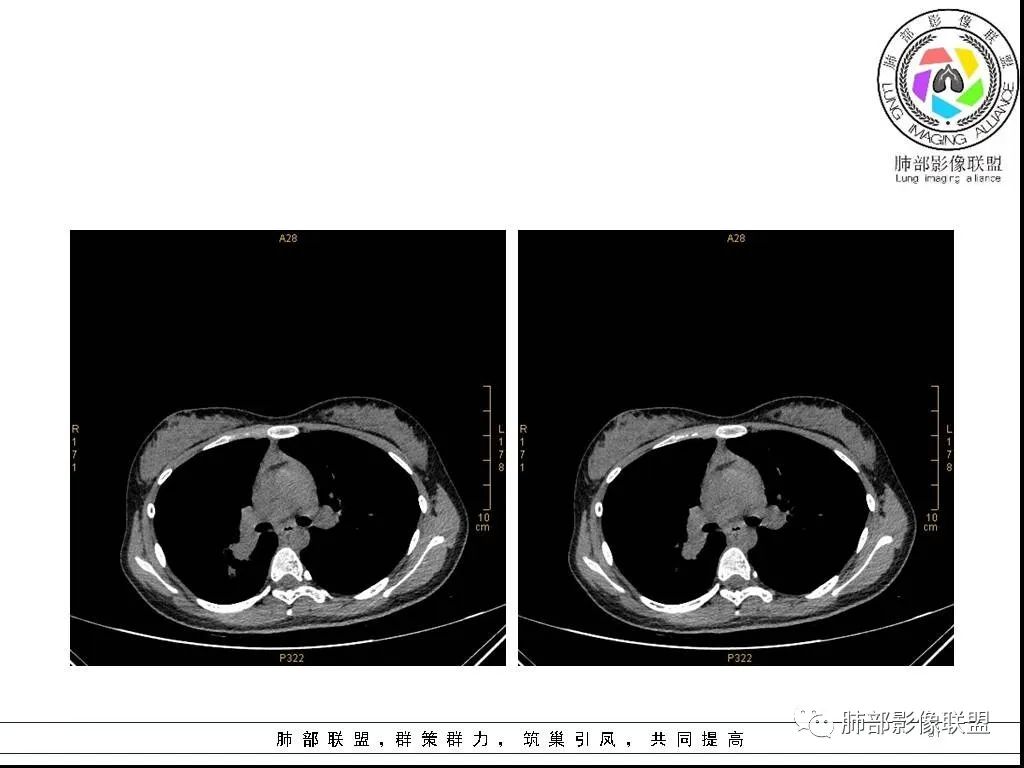

右肺炎症性病变1例CT影像讨论

年轻女性,病程长,咳嗽少痰4个月,辅检未见特殊,CT:右肺团块影,跨叶,主体在下叶背段,外大内小,边缘以膨隆为主,部分平直内收,深分叶,周围有模糊晕,可疑卫星灶,胸膜增厚,糊墙,支气管近端部分进入,粘液栓,有坏死空腔,内壁光整,部分血管侵蚀,强化不均,延迟,明显;同侧R10、7、R4淋巴结肿大,考虑肉芽肿炎,结核,需要与肿瘤鉴别:16岁,女性,诊断肿瘤需要勇气,跨叶多见于炎性,需要进一步活检。

16岁女性,咳嗽,咳痰4月,无发热,白细胞不高,炎性指标(CRP,PPT)不高,血沉增高(75mm/h)。影像表现:右肺胸膜下不规则肿块影,边缘平直,U型凹陷,桃尖征为主,纵隔窗部分层面似有多个结节融合感,近端支气管扩张,堵塞,局部呈鬼脸样改变。边缘可见长短不一毛刺影,周围见晕征,远端见多个小结节卫星灶。胸膜大面积反应性增厚,增强后不均匀中度渐进性强化,局部干酪样坏死可能(CT值-32~-15)内部血管走行较正常,破坏不明显。 医学百科网 | YxBaike.Com

这个病例的特点:病灶贴近斜裂内侧区域,范围较大,直达肺门区。右肺上叶,前、尖、后段前移,病灶嵌塞于上叶后段支气管的后下方区域,未能跟踪到病灶与叶段支气管关系。应当怀疑有额外的支气管存在,也就是副叶。因为这么大的病灶,这么粗大肺动脉进入,伴行的支气管应当比较粗大,但是没能观察到较大的支气管与其相延续。